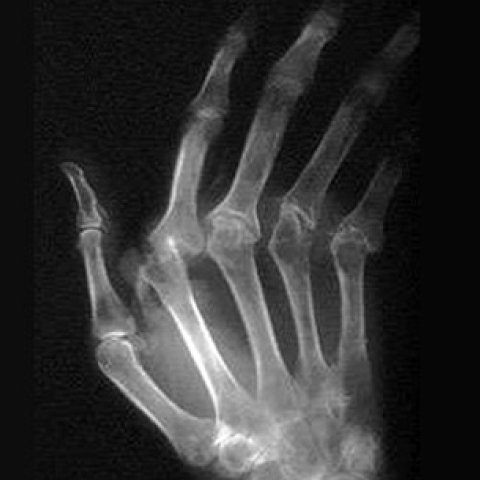

Νέα στοιχεία για τη ρευματοειδή αρθρίτιδα

Ομάδα επιστημόνων πιστεύει ότι η λύση βρίσκεται στα γονίδια